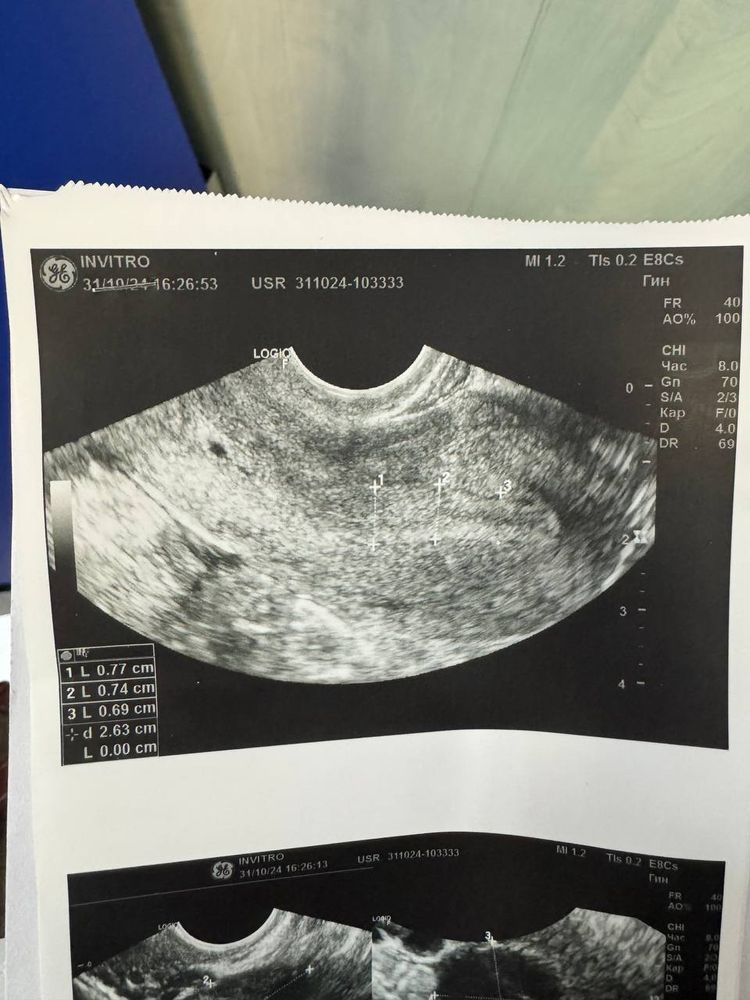

Задержка М и нет БДевочки,у меня всегда овуляция на 18ДЦ. В этот раз сходила на узи на 17ДЦ и на узи увидели ЖТ. Врач сказал, что в этот раз овуляция ранняя. Сегодня 31 ДЦ ,а месячных нет и тест делала вечером он кристально чистый(( скажите пожалуйста,что это может бы б? Было ли такое у кого нибудь ?

ALINA , еще меня смущает снимок с ЖТ по середине белая полоска какая то. Может быть такое ,что врач вообще ошибся ? И никакой овуляции не было ?

Тайный , УЗИ действительно похоже на ЖТ, а полоска,ну бывает такое, ЖТ же в принципе не может иметь ровных границ, оно как бы рваное после выхода ЯК, возможно это просто кусочек ткани болтается там..ну и ещё как вариант возможно сейчас у вас киста жёлтого тела, при таком раскладе 2 фаза может удлиниться, но это не критично..